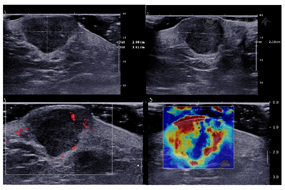

皮肤肿物及引流区淋巴结超声提示:右侧会阴部及肛门偏左侧皮下软组织内分别见混合回声区,大小25 mm×11 mm,13 mm×9 mm,形态不规则,边界不清晰,内部回声不均匀。周边皮下软组织肿胀,回声增高。病灶内部及周边可见血流信号。剪切波弹性成像提示病灶较周围组织硬(图2、图3)。双侧腹股沟区可见数个低回声区,较大者大小28 mm×17 mm,形态不规则,边界尚清晰,内部回声不均匀,皮髓质分界不清,未见淋巴门样结构。内部见血流信号(图4)。右侧会阴部及肛门偏左侧皮下软组织内实性结构,恶性病变可能性大。双侧腹股沟区实性结构,考虑异常淋巴结。